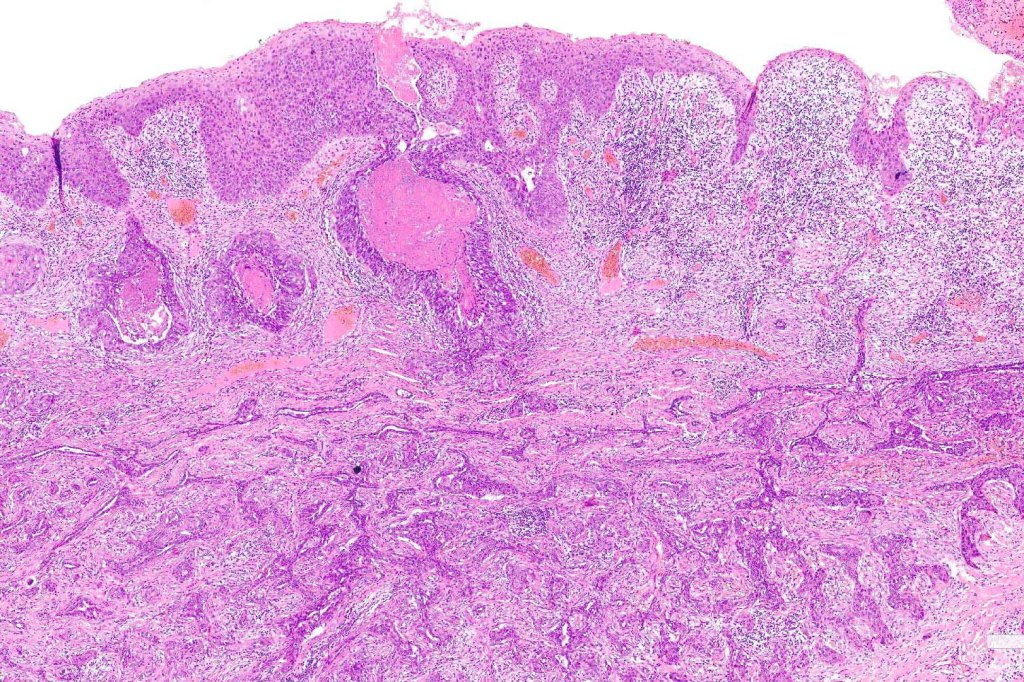

•Ulceration and solar elastosis are common

•Widely infiltrating biphasic tumor

•Superficial SCC

•Adenocarcinoma in deeper reaches

•Often extends to the subcutaneous fat